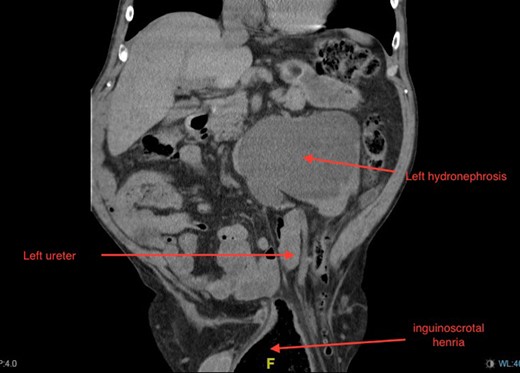

Non-contrast CT of the chest, abdomen and pelvis was performed on admission looking for malignancy considering his visible haematuria and significant unintentional weight loss. This demonstrated severe bilateral hydronephrosis and hydroureter, which was more prominent on the left side (Figs 2–4). The left ureter tapered in the pelvis and neither the bladder nor either ureter was seen in the inguinal canal and a large, left-sided inguinoscrotal hernia was seen containing distal colon. Bilateral loss of renal cortical thickness, a potassium of 6.0 mmol/L and an eGFR of 9 mL/min was suggestive of chronically obstructed kidneys.

Coronal section of CT demonstrating bilateral hydronephrosis and collapsed bladder with urethral catheter in situ.